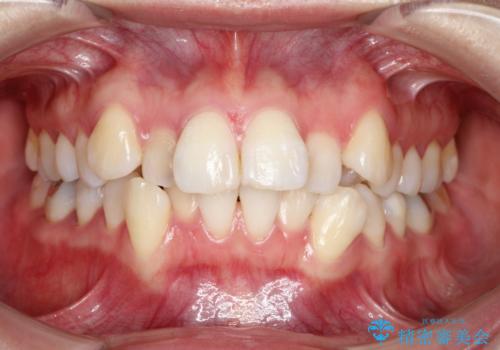

- 前歯のデコボコと上顎の前突感による口の閉じにくさを気にして来院された患者様です。

目立たない装置を希望されたので、上顎が裏側装置のハーフリンガルを選択し、上下左右の小臼歯(計4歯)を抜歯して矯正治療を行うこととしました。